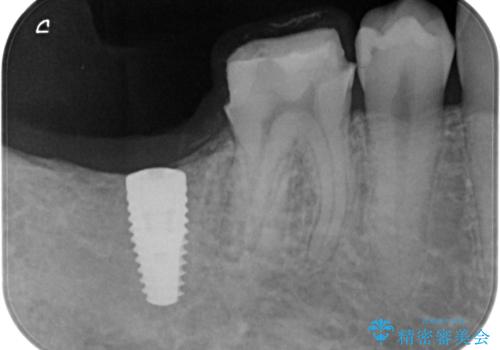

右下の被せ物を外し虫歯を除去したところ虫歯が深く保存が難しい状態だったので抜歯を行いました。

手前の銀の詰め物のところは除去して拡大鏡下で虫歯を取り除き、ジルコニアクラウンで治療を行いました。

抜歯したところは抜歯後骨の治癒を待ち、CTを撮影しインプラント治療ができる事(骨の厚みなど)確認し治療を行いました。